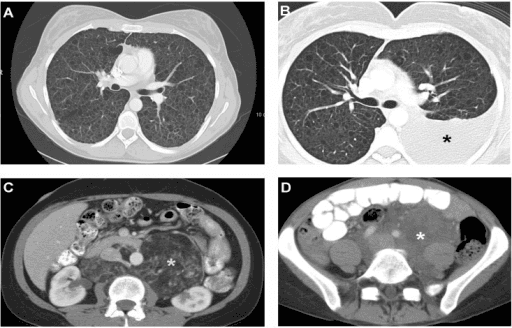

What's the Diagnosis?